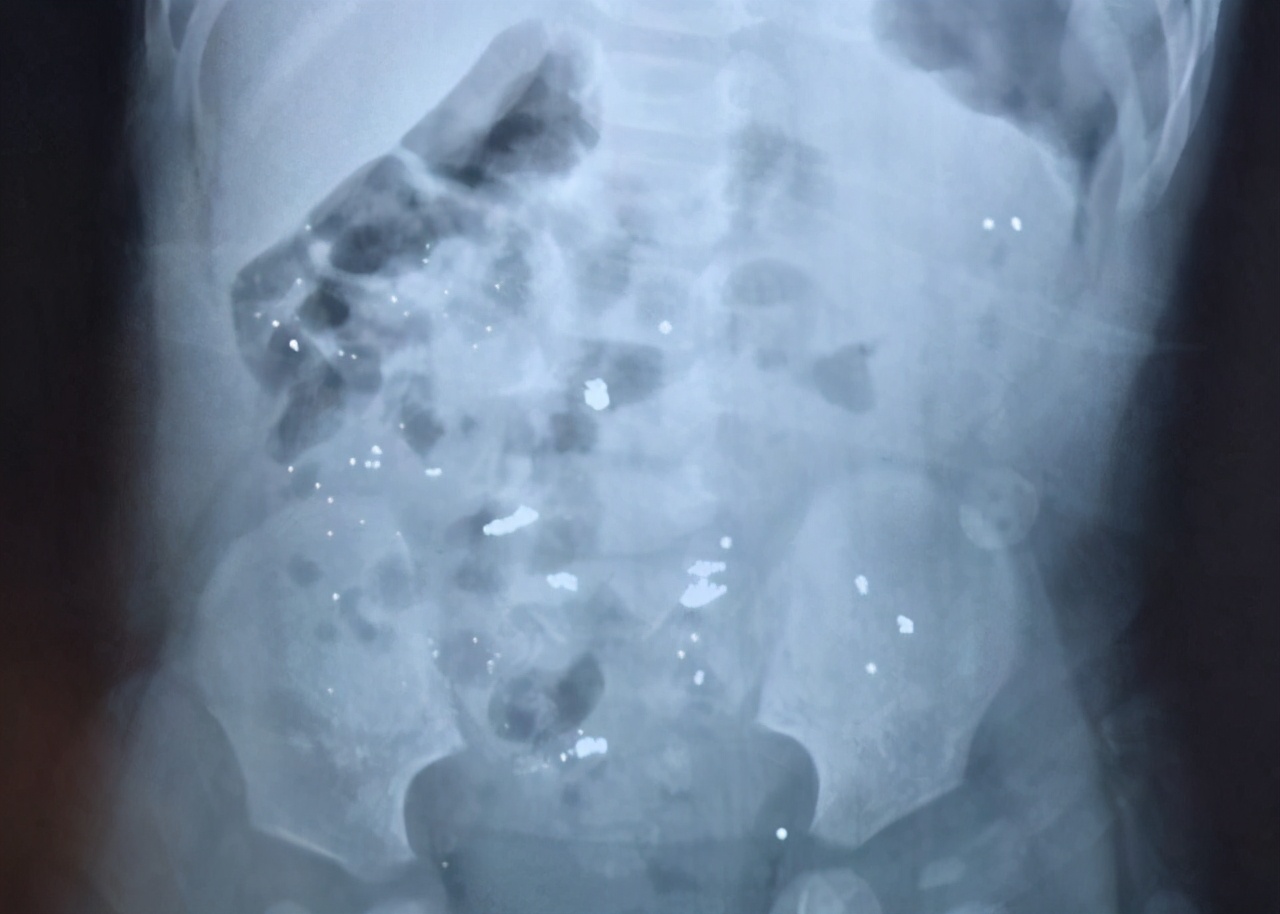

如果吞食的水银时间长,可拍腹部X光片来确定水银残留位置,由于水银比重高,一般还在胃里面。此时可洗胃或导泻;一般导泻可口服50%硫酸镁或甘露醇。